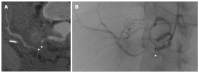

Orthotopic liver transplantation (OLT) represents a major treatment for end-stage chronic liver disease, as well as selected cases of hepatocellular carcinoma and acute liver failure. The ever-increasing development of imaging modalities significantly contributed, over the last decades, to the management of recipients both in the pre-operative and post-operative period, thus impacting on graft and patients survival. When properly used, imaging modalities such as ultrasound, multidetector computed tomography, magnetic resonance imaging (MRI) and procedures of direct cholangiography are capable to provide rapid and reliable recognition and treatment of vascular and biliary complications occurring after OLT. Less defined is the role for imaging in assessing primary graft dysfunction (including rejection) or chronic allograft disease after OLT, e.g., hepatitis C virus (HCV) recurrence. This paper: (1) describes specific characteristic of the above imaging modalities and the rationale for their use in clinical practice; (2) illustrates main imaging findings related to post-OLT complications in adult patients; and (3) reviews future perspectives emerging in the surveillance of recipients with HCV recurrence, with special emphasis on MRI.